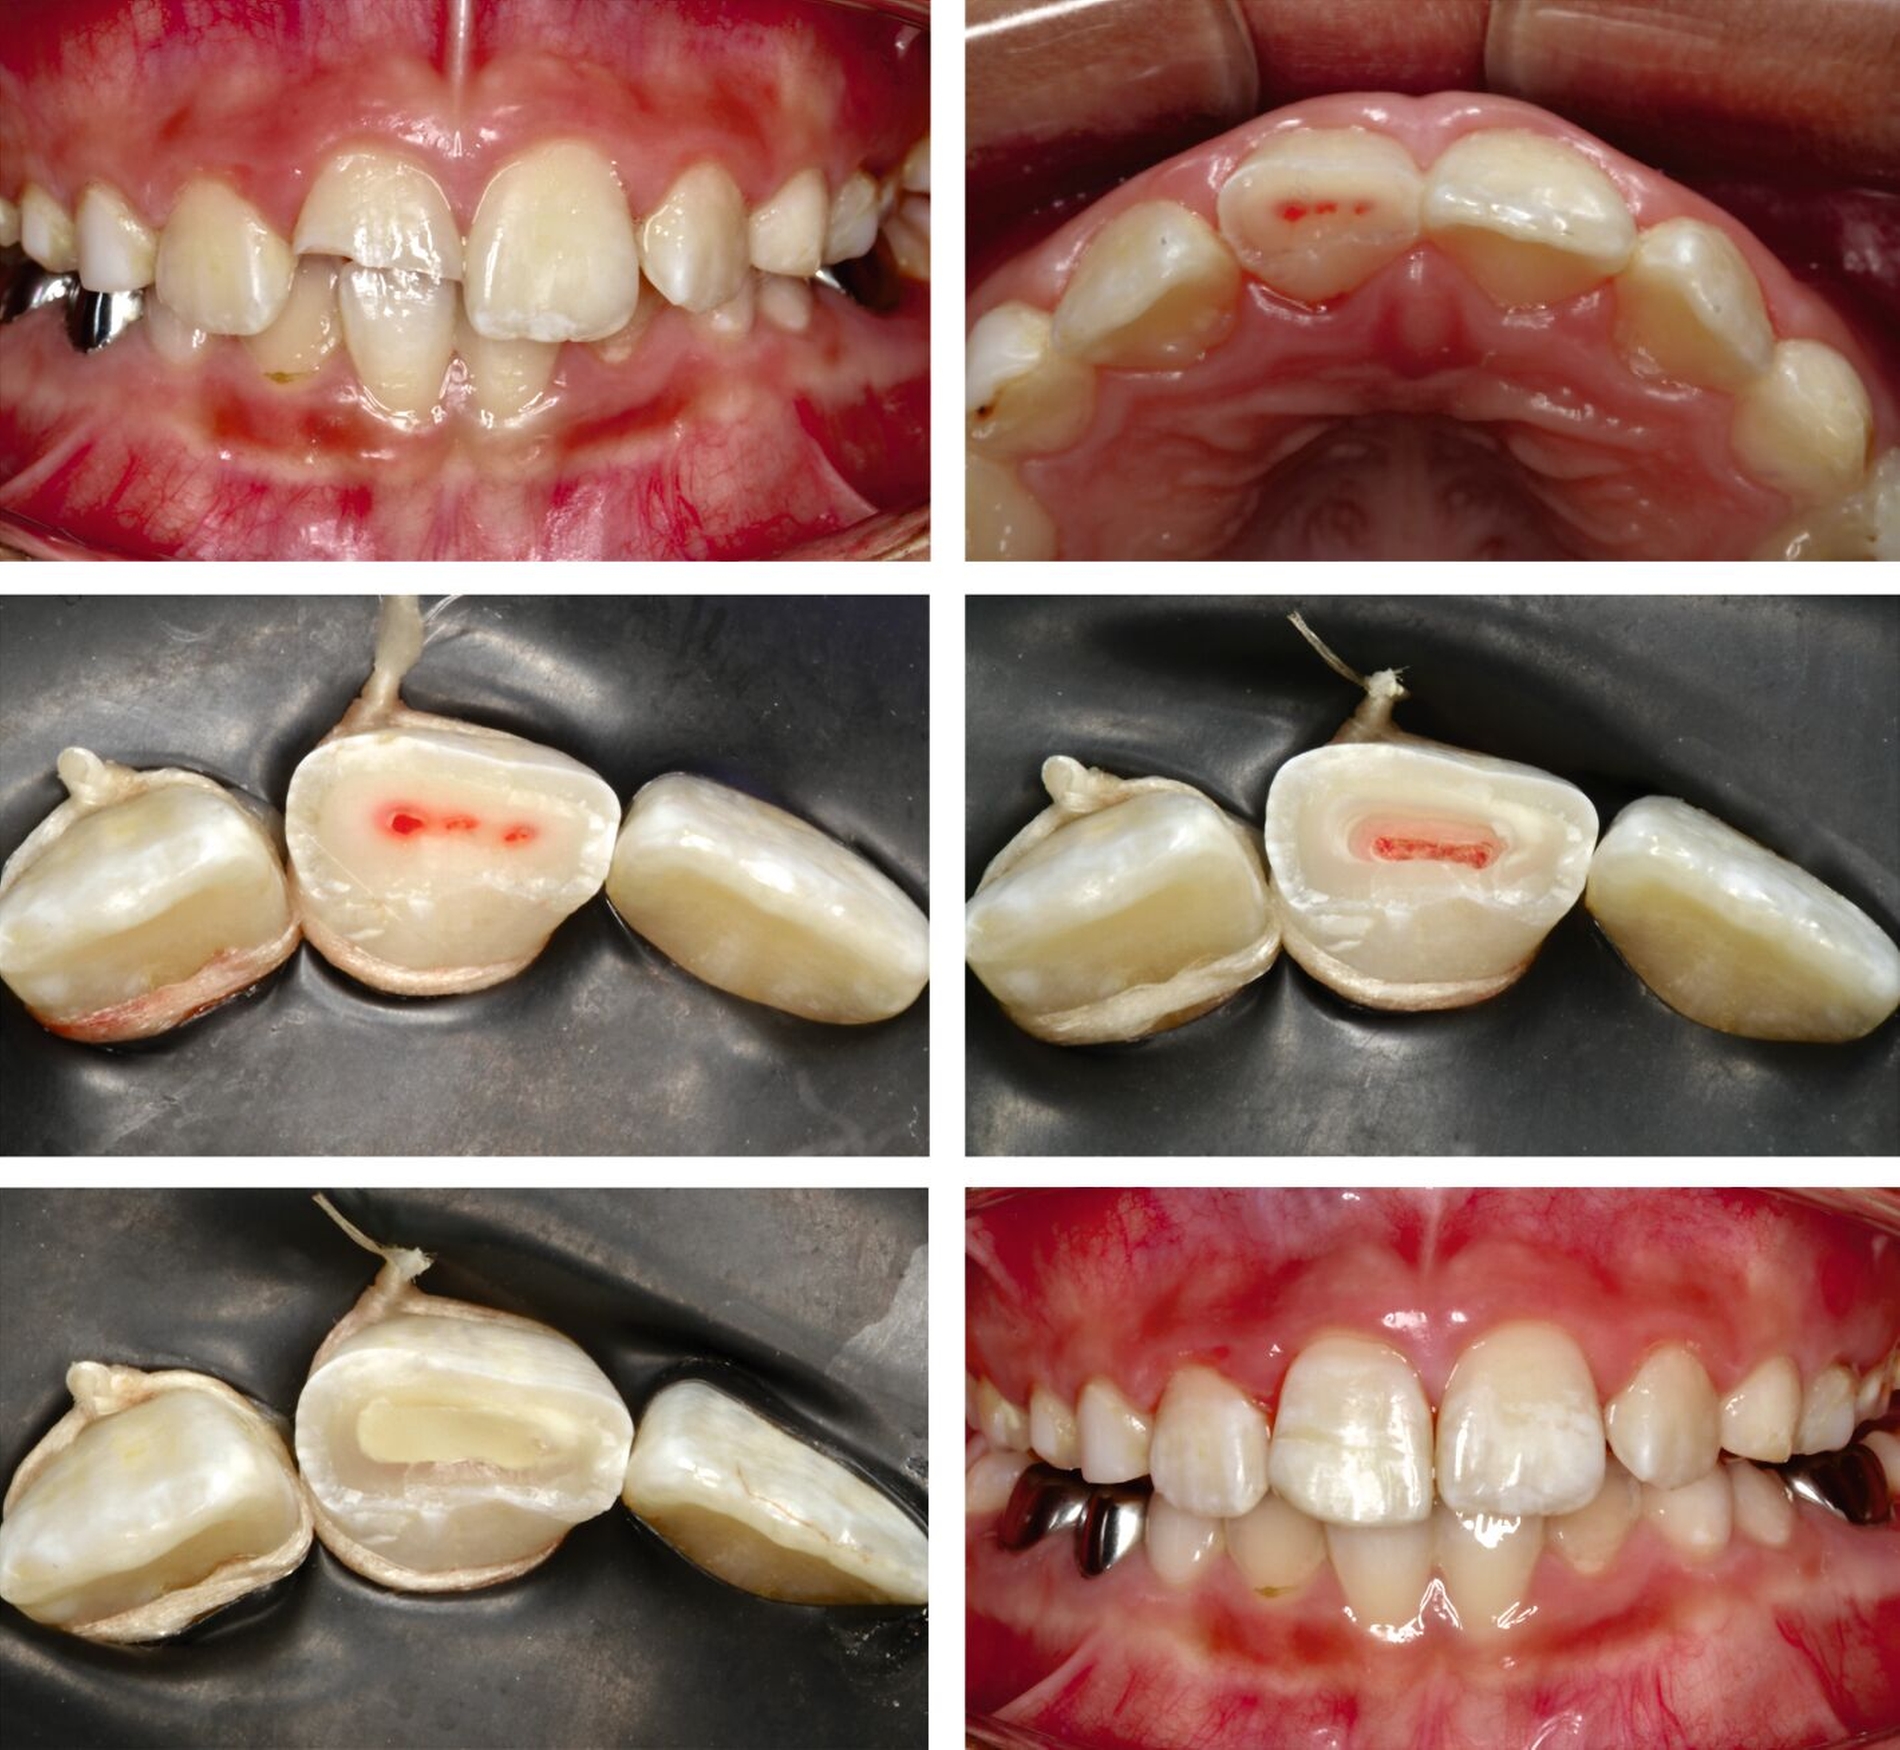

Da der Zahn exakt reponierbar ist, ist bei jugendlichen Zähnen eine Heilung durch Revaskularisation wahrscheinlicher als nach lateraler Dislokation. Dies gilt insbesondere für Zähne, die sich zum Zeitpunkt des Traumas in festsitzender KFO-Behandlung befunden haben (Abbildung 3). Die speziellen mechanischen Verhältnisse können eine Extrusion gleich mehrerer benachbarter Zähne bewirken, wobei in solchen Fällen Komplikationen ausbleiben können, was sich durch eine verstärkte Mundhygiene während der KFO und eine vorbestehende Erweiterung des Foramen apikale durch eine KFO-bedingte Wurzelresorption erklären lässt.

Bei ausgeprägten Extrusionen sollte bei Zähnen mit abgeschlossenem Wurzelwachstum beziehungsweise weitgehend geschlossenem Foramen apikale in Anlehnung zur Empfehlung für laterale Dislokationen eine Wurzelkanalbehandlung eingeleitet werden.